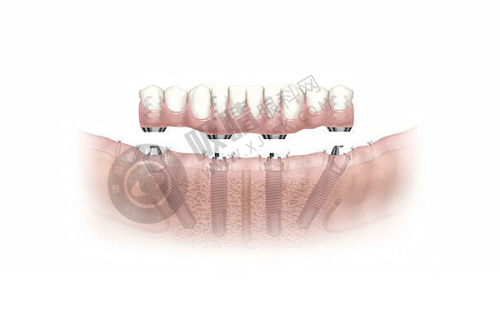

陕西省人民医院口腔科可开展全口数字化种植、ONLY 植骨术、骨劈开术、GBR 手术、即刻种植、上颌窦外提升等高难度的种植技术。

西安交大口腔正畸科提供3D 数字化方案设计,修复科引进德国即刻种植技术